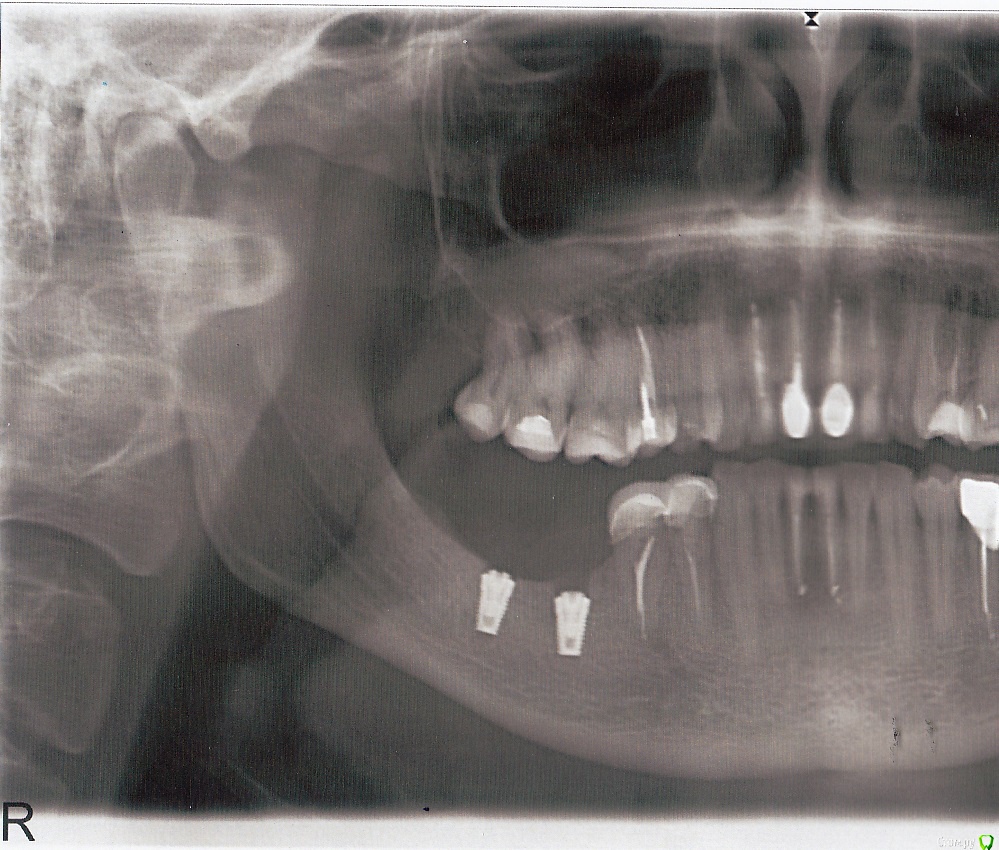

serrr Опубликовано 2 сентября, 2015 Поделиться Опубликовано 2 сентября, 2015 Добрый день.28.08.2015 мне установили импланты нижних 6-ки 7-ки . Во время сверления отверстия под 7-ку было кратковременное болевое ощущение, будто разряд электричества. Врач сказал, что такое бывает. Где-то спустя сутки или чуть более онемела часть губы до подбородка. Потеря чувствительности неполная. Идет пятый день после операции, видимого улучшения чувствительности нет. Сделал панорамный снимок. Врач, который делал операцию снимок смотрел, сказал, что нерв не задет и примерно через неделю онемение пройдет и чувствительность восстановится. Посмотрите, пожалуйста, снимок. Это нормальное явление и само пройдет, или необходимо менять имплант на более короткий или еще что-то?Спасибо! Ссылка на комментарий

Aquarius Опубликовано 2 сентября, 2015 Поделиться Опубликовано 2 сентября, 2015 Шестерку хорошо притопили)) Семерку можно и подвыкрутить. По этому снимку до нерва на самом деле расстояние есть Ссылка на комментарий

Aquarius Опубликовано 2 сентября, 2015 Поделиться Опубликовано 2 сентября, 2015 (изменено) На мой взгляд, это нехорошо.Еще большая убыль кости будет вокруг импланта. Мысленно нарисуйте высоту коронок до верхних зубов. Даже с учетом, того, что рот полуоткрыт Изменено 2 сентября, 2015 пользователем Aquarius Ссылка на комментарий

doca Опубликовано 4 сентября, 2015 Поделиться Опубликовано 4 сентября, 2015 нет ничего страшного в том, что 6-й на снимке смотрится заглубленныи, возможно планировали обойтись без костной пластики и адекватная ширина кости была на этом уровне.Высота коронки , особенно при соединении с 7-м никакого отрицательного влияния на срок службы импланта не окажет. 2 Ссылка на комментарий

serrr Опубликовано 7 сентября, 2015 Автор Поделиться Опубликовано 7 сентября, 2015 Онемение так и не проходит, сегодня сделал КТ. Вот результаты https://yadi.sk/d/8pBNKzR2ivrDcПопросил в клинике посмотреть результаты. Он сказал, что нужно чуть-чуть выкрутить 7-ку, а то давит на канал. В среду иду с результатами КТ на прием к врачу, который ставил мне импланты. Послушаю, что он скажет. Но я буду просить немного открутить 7 ку. Ссылка на комментарий

Bier Опубликовано 7 сентября, 2015 Поделиться Опубликовано 7 сентября, 2015 открутить уже мало толку, скорее вынуть и поставить покороче. Ссылка на комментарий